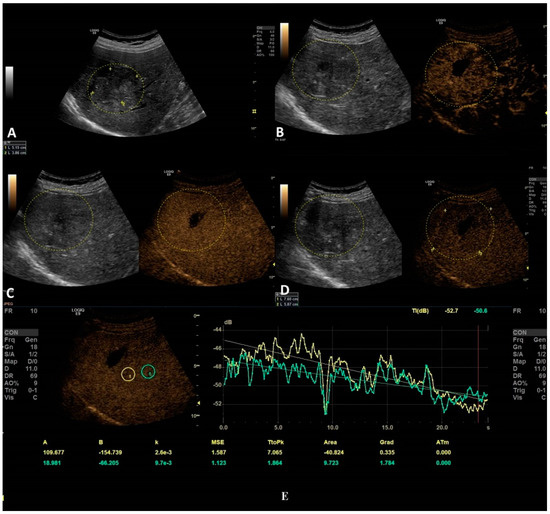

Figure 4. In this setting, a benign lesion was assessed, as depicted in B-mode in frame (A). In frames (BD) are depicted the vascular arterial, portal, and late phases of CEUS with different enhancement characteristics, respectively. In frame (D), the enhancement pattern is not recognizable; thus, TIC analysis (E) was applied. The results did not show us any objective washout phenomena (the graphs are not intersecting one another).